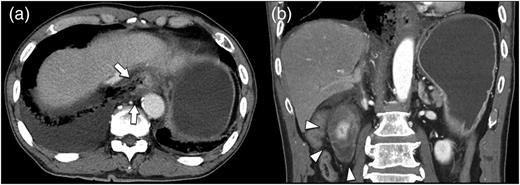

A 67-year-old man presented with vomiting and epigastric pain. He had a history of duodenal ulceration and emergent laparotomies for repeated duodenal perforation, resulting in stenosis of the second portion of the duodenum. The patient was referred to our hospital for evaluation of vomiting. He exhibited upper abdominal guarding on physical examination. His blood chemistry revealed no abnormal findings with the exception of a mild increase in the C-reactive protein level (2.1 mg/dl). His nutritional state was maintained. Dynamic computed tomography revealed massive right pleural effusion with pneumomediastinum. A defect was present in the lower esophagus, his stomach was dilated and the proximal duodenal wall was thickened (Fig. 1a and b). Thoracoscopic exploration was performed prior to laparotomy in the left semi-lateral decubitus position with 2 ports under differential lung ventilation. The right pleural cavity was severely contaminated with brownish pleural effusion and was thus irrigated under thoracoscopy, but the perforated site was not identified. Laparotomy was then performed, which revealed a 4-cm longitudinal defect on the right side of the lower esophagus via esophageal hiatus (Fig. 2). The defect was closed by direct suturing with 4-0 pieces of monofilament strings and reinforced by using the greater omentum. The surgical field was irrigated, and a feeding jejunostomy was created. A 19F blake drain (Ethicon, Inc., Sommerville, NJ, USA) was placed in the lower mediastinal space via abdominal cavity, and a 20F thoracic drain (Sumitomo Bakelite Co., Ltd, Tokyo, Japan) was placed in the right thoracic cavity via the port site. The position of the mediastinal drain was cranially adjusted using the thoracoscopy (Fig. 3a and b). Extubation and enteral feeding via the jejunostomy tube were initiated on Day 2. Endoscopic dilatation was performed due to esophageal stenosis. The patient was discharged on Day 60 without mediastinitis, pneumonia or empyema.

Chest and abdominal computed tomography findings. (a) Horizontal cross section. The right wall of the abdominal esophagus is perforated (arrows). (b) Coronal section. The duodenal wall is markedly thickened (arrowheads).